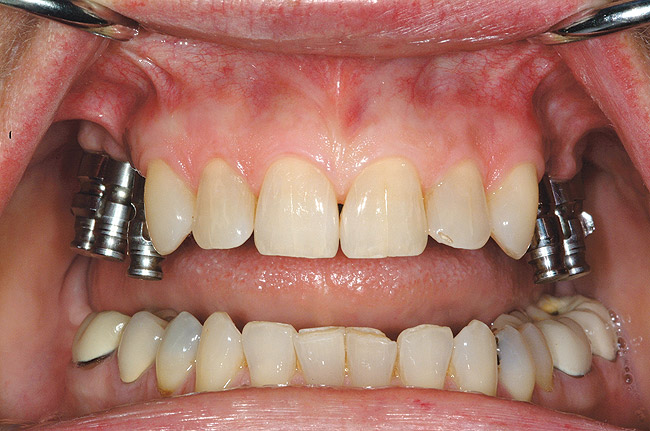

Figure 5  Locator abutments placed on implants can also be used for an implant-assisted prosthesis.

Figure 5